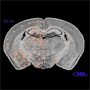

photomicrograph of

coronal section in

Macaca mulatta